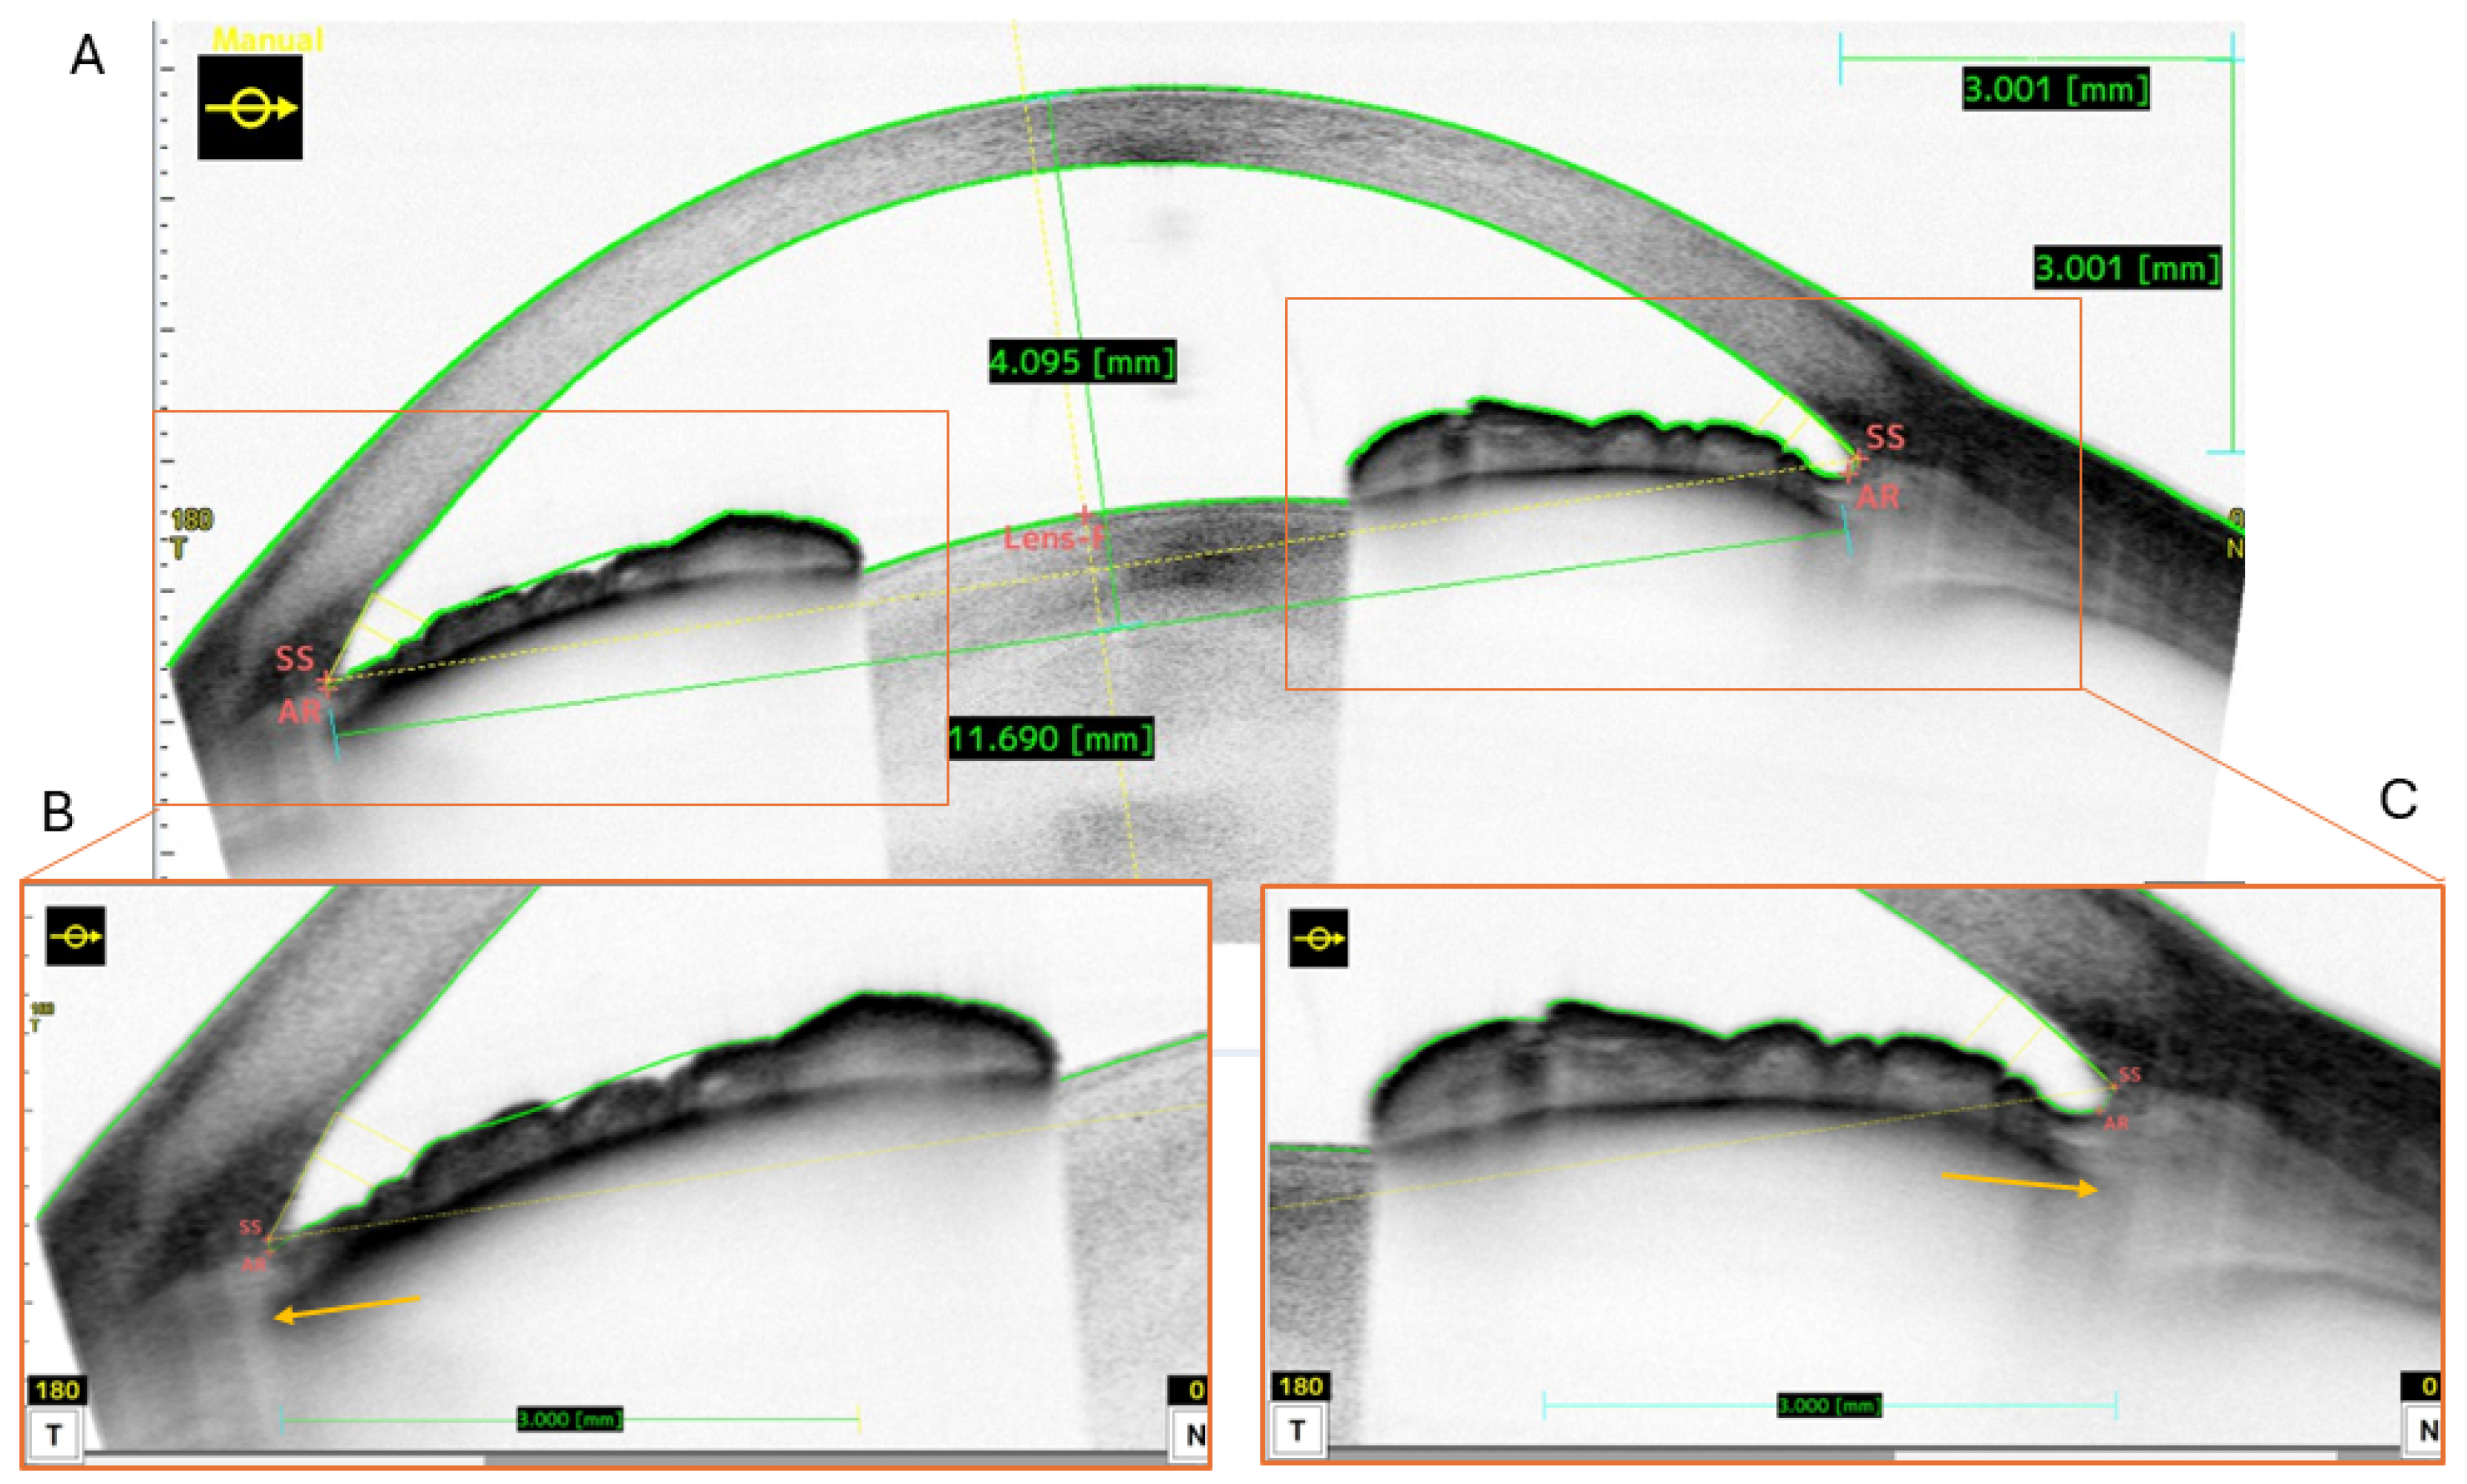

2.2. Measurement Method

- Dong, J.; Yao, J.; Chang, S.; Kanclerz, P.; Khoramnia, R.; Wang, X. Evaluation of Ocular Diameter Parameters Using Swept-Source Optical Coherence Tomography. Medicina 2023, 59, 899. [Google Scholar] [CrossRef]

- Naujokaitis, T.; Auffarth, G.U.; Łabuz, G.; Kessler, L.J.; Khoramnia, R. Diagnostic Techniques to Increase the Safety of Phakic Intraocular Lenses. Diagnostics 2023, 13, 2503. [Google Scholar] [CrossRef]

- Patyal, S.; Yadav, A.K.; Anthony, H.; Ansari, F. Iridociliary measurements using the Anterion swept-source optical coherence tomography. Indian J. Ophthalmol. 2022, 71, 109–112. [Google Scholar] [CrossRef] [PubMed]